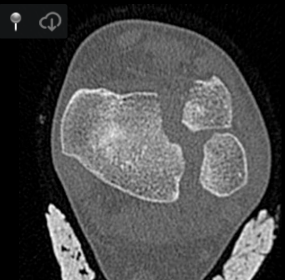

• Fracture Salter III du tibia

Tilaux tilau tillau tillaud tilau tibaut thibaut till cheville ankle